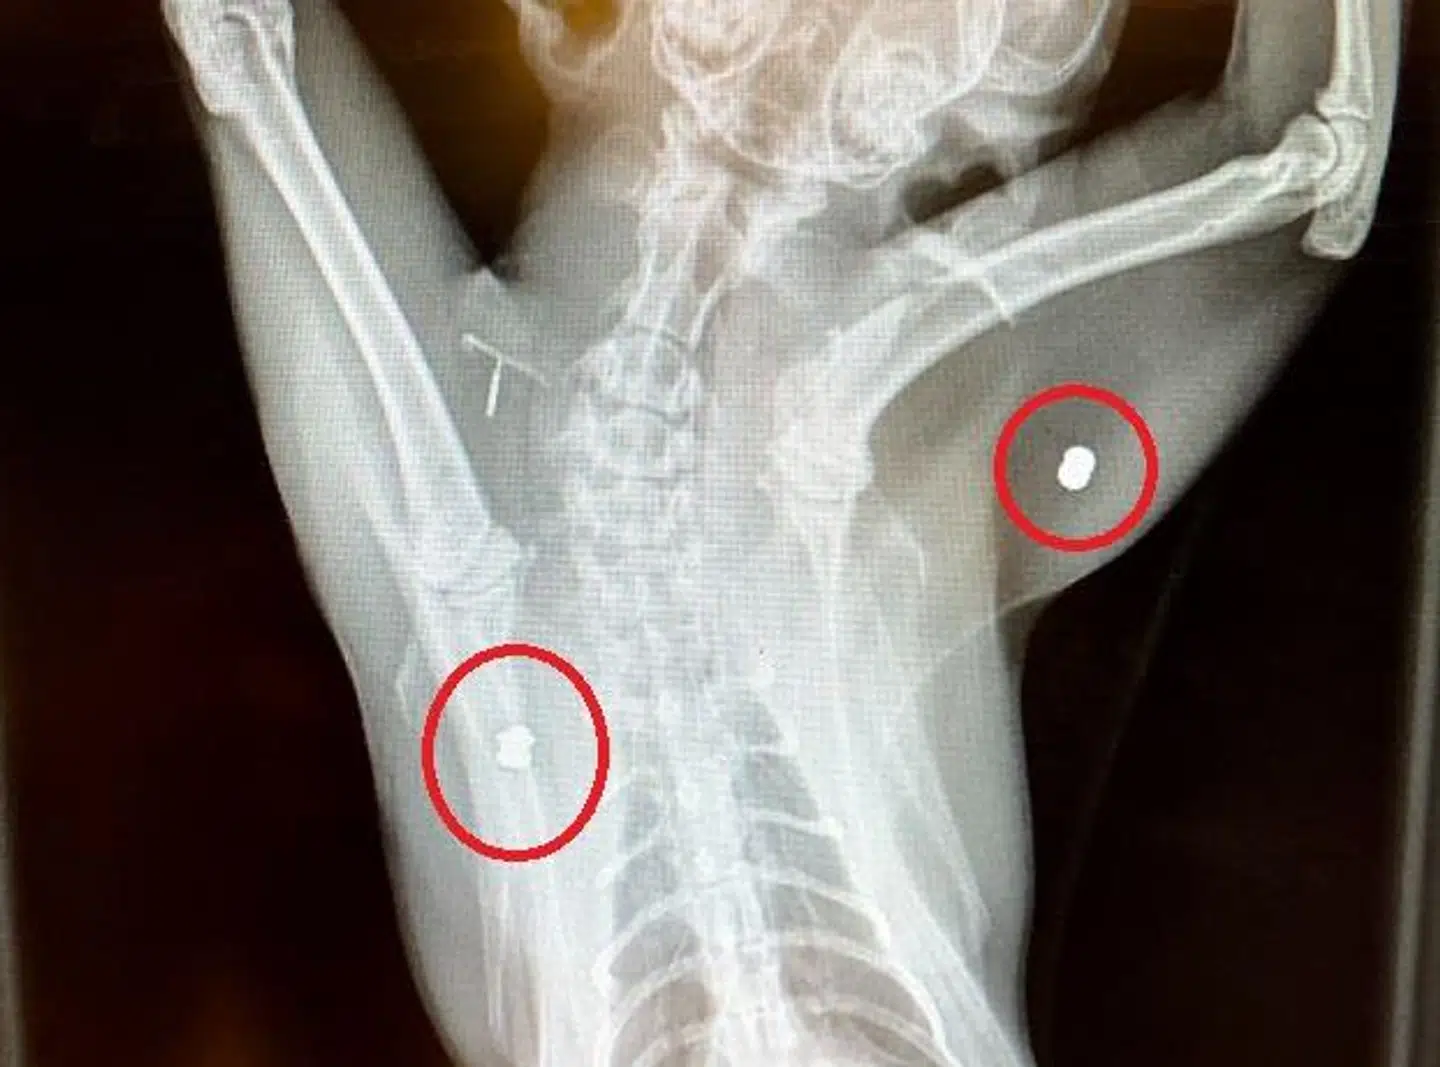

Røntgenbilleder viste, at katten var blevet ramt i begge sider af kroppen, og da det ene hagl havde sat sig fast i muskulaturen, har den haft store gener.